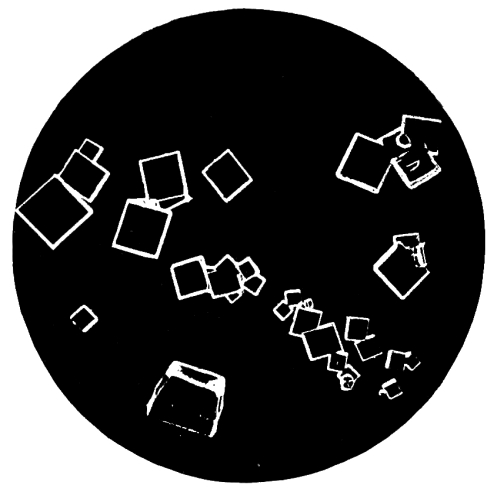

| 28. | Photo-micrograph of Crystals of Oxalic Acid | 258 |

| 29. | Photo-micrograph of Crystals of Oxalic Acid | 259 |